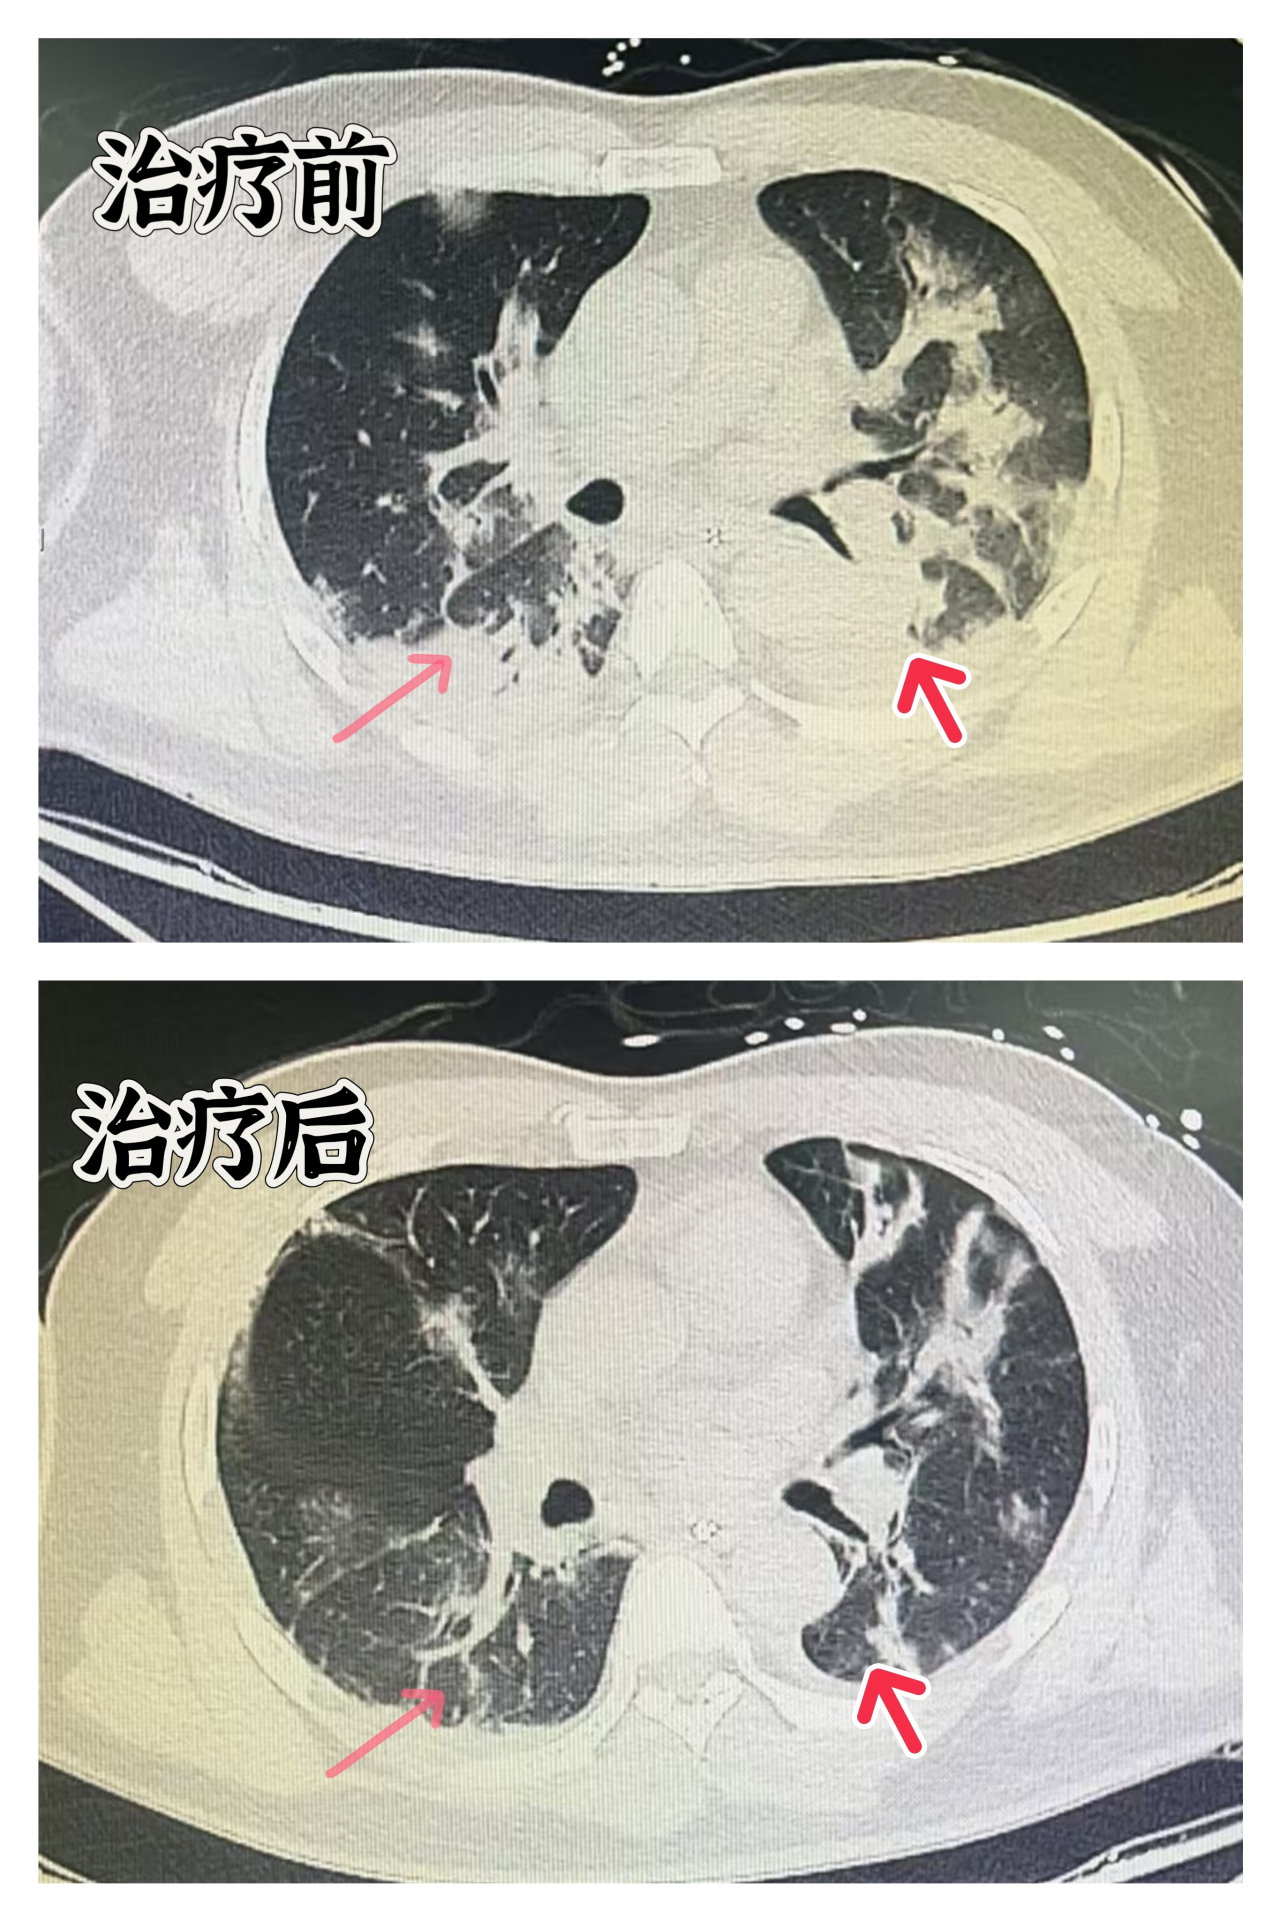

检测结果显示流感病毒抗原呈阳性,确诊为甲型流感病毒感染并发重症肺炎。影像学检查显示,患者的肺部已经出现“白肺”现象。随着病情的迅速恶化,患者出现了呼吸衰竭和循环衰竭的症状。

在重症医学中心ECMO团队的全力救治下,通过5天左右的ECMO心肺支持治疗,患者的肺部病变有了明显好转,目前正在康复中。